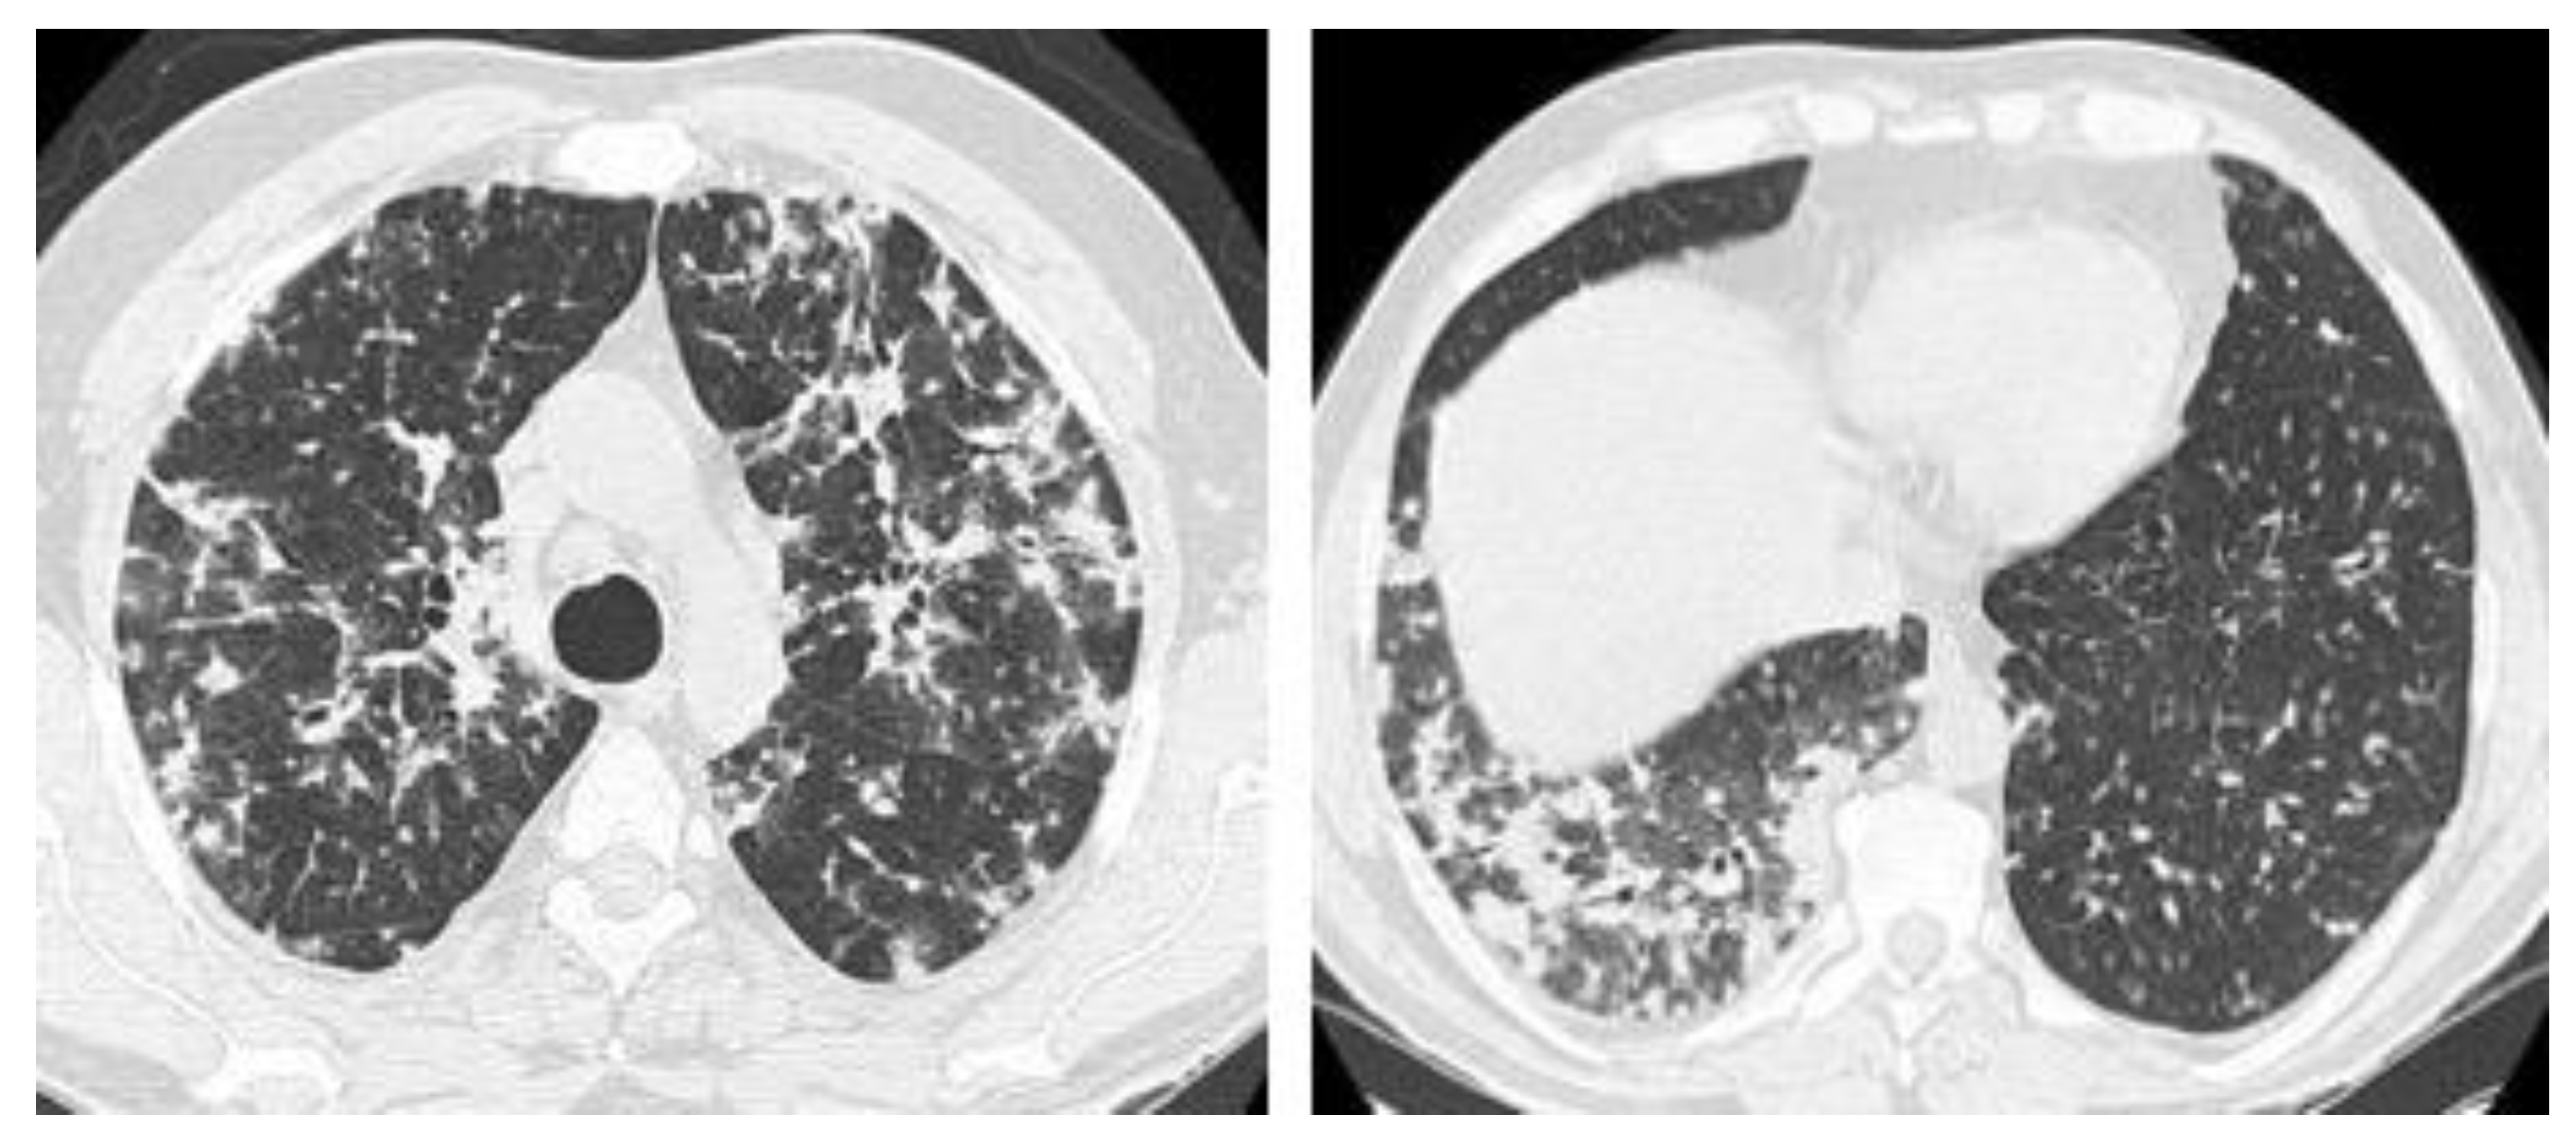

2.3. Chronic Cavitating Disease

2.5. Mixed Pattern